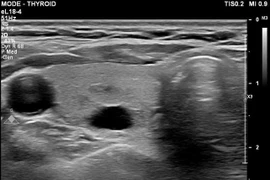

Top thực phẩm tốt cho tuyến giáp

Bổ sung hạt điều, hạt bí, trái cây tươi và cá biển để duy trì sức khỏe tuyến giáp, giảm nguy cơ viêm nhiễm và cân bằng hormone tự nhiên.